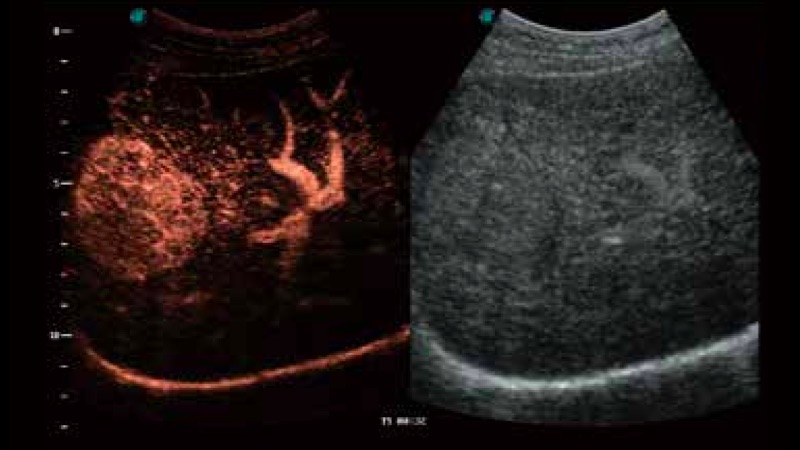

開立醫(yī)療通過不斷的技術(shù)創(chuàng)新,為大眾的生命健康提供持續(xù)關(guān)愛。P12 Plus采用全新一代超聲成像平臺,新平臺旨在將真實還原組織解剖結(jié)構(gòu)作為首要目標(biāo)。平臺采用全新集成化硬件模塊,搭載新一代芯片,系統(tǒng)性能得到大幅提升,為您的診斷提供了豐富的臨床信息。優(yōu)異的圖像表現(xiàn),豐富的探頭配置,全面的應(yīng)用功能,為您日常診斷提供了可靠的助手。

P12 Plus

彩色多普勒超聲診斷系統(tǒng)